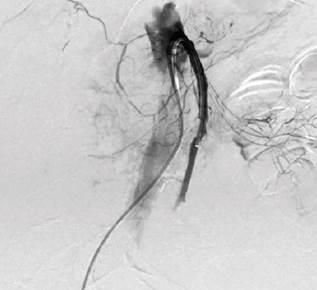

La paciente fue llevada inmediatamente a un aortograma abdominal, una arteriografía selectiva de los vasos abdominales y una tromboembolectomía por radiología intervencionista, donde se encontró una oclusión de las arterias hepática común, mesentérica superior y mesentérica inferior (Figura 2). Mediante catéteres índigo 6 Fr y 8 Fr se practica en múltiples ocasiones una trombectomía por aspiración y se obtienen coágulos de aspecto agudo y subagudo, con la cual se logra solamente revascularizar el tercio proximal de esta arteria con flujo de salida por arcada pancreatoduodenal que reperfunde la arteria hepática propia y la primera rama yeyunal (Figura 3). No se lograron revascularizar los dos tercios distales de la arteria mesentérica superior debido al pésimo flujo de salida. Inmediatamente después del procedimiento, la paciente fue llevada a CPRE; en la segunda porción duodenal se observó un marcado edema que no permitió la visualización de la papila, por lo que se suspendió el procedimiento.

Fuente: archivo de los autores.

Figura 2 Arteriografía selectiva de vasos abdominales que denota una oclusión de las arterias hepática común, mesentérica superior y mesentérica inferior.

Figura 3 Reperfusión de la arteria hepática propia y primera rama yeyunal.